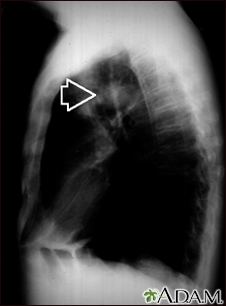

Pulmonary mass - side view chest x-ray